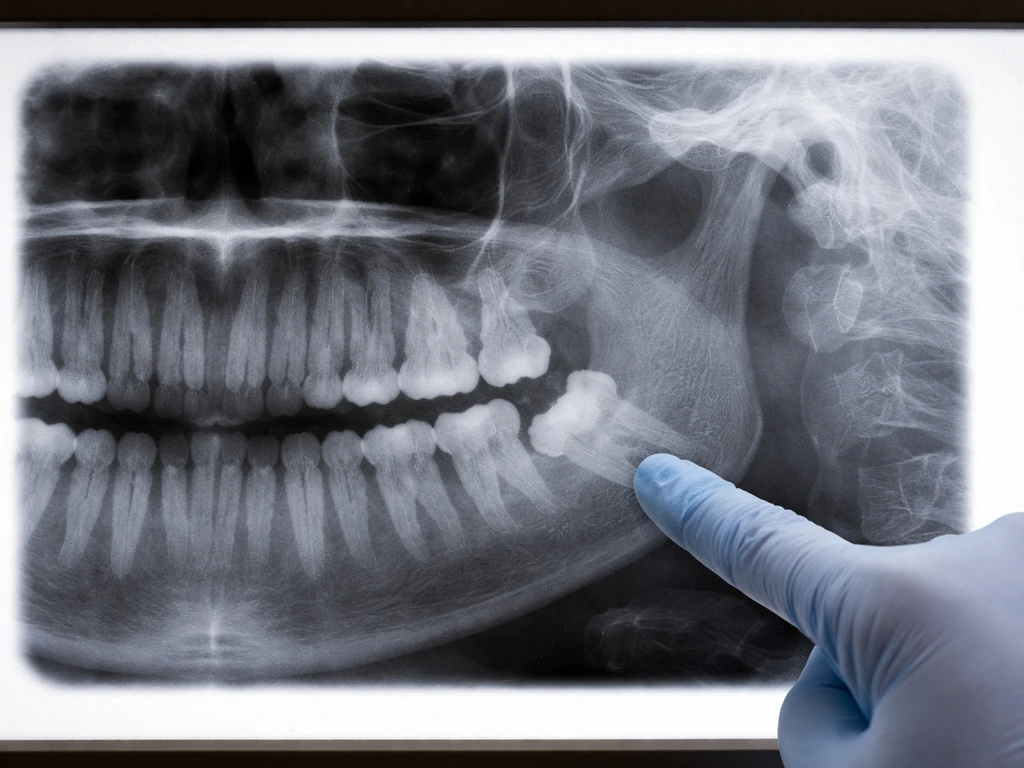

- Impaction: when the wisdom tooth is angled or blocked and cannot fully erupt. Pain can be intense, persistent, and may involve the ear or jaw joint. An impacted tooth often only shows up clearly on an X-ray.

When you arrive at the dentist, expect a visual exam of the eruption site, probing around the gum flap to check for pocket depth and tenderness, and almost certainly an X-ray (panoramic or periapical) to see how the tooth is positioned, whether it is impacted, and whether any adjacent teeth or bone are affected. This is the only reliable way to know what is actually happening under the surface.

Treatment depends entirely on what the exam and X-ray reveal. There is no one-size-fits-all answer, but here are the most common paths.

If you have already had one wisdom tooth removed and are wondering about the remaining ones, each tooth should be evaluated individually on its own position, eruption path, and symptom history. There is no rule that all four must come out, but there is also no natural regeneration or self-correction process that will fix an impacted or chronically inflamed site. The biology is what it is, and having a dentist track it with periodic X-rays is the most practical way to stay ahead of problems rather than reacting to them.